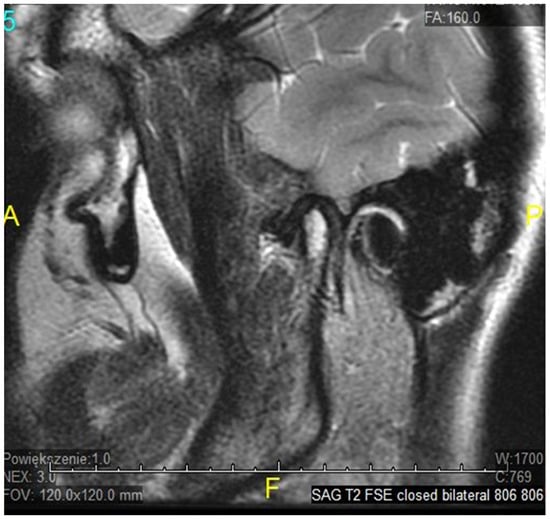

- Litko-Rola, M.; Szkutnik, J.; Różyło-Kalinowska, I. The importance of multisection sagittal and coronal magnetic resonance imaging evaluation in the assessment of temporomandibular joint disc position. Clin. Oral Investig. 2021, 25, 159–168. [Google Scholar] [CrossRef]